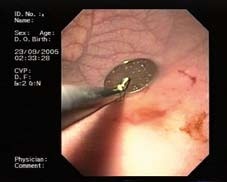

Endoskopické vyšetření horního zažívacího traktu u dětí je třeba provést v celkové anestezii, v případě CT se zajištěním dýchacích cest endotracheální intubací, abychom zabránili vdechnutí (aspiraci). Výkon by měl být prováděn na dobře vybaveném endoskopickém pracovišti. Vedle zkušeného endoskopisty a anesteziologa tu hraje velkou roli i asistence zkušené endoskopické sestry. K extrakci CT se používají různá akcesoria - kličky, kleště, košíky, tripody (obr. 2-4). V případě extrakce ostrých předmětů je vhodné použít overtube (kryt, do kterého je ostré CT vzato, aby nedošlo k poranění stěn zažívacího traktu) (obr. 5).